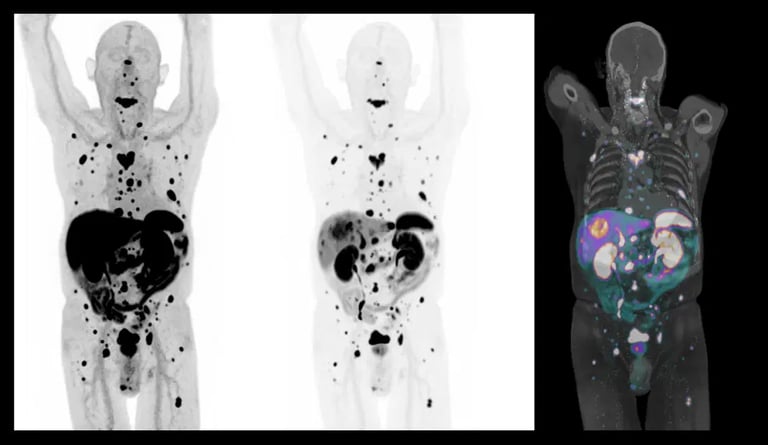

Uma dúvida comum entre os pacientes é sobre quais exames são necessários para avaliar a extensão da doença. Muitas pessoas acreditam que exames mais modernos, como o PET-CT, são sempre a melhor escolha, mas isso não é uma regra. Cada exame tem indicações específicas e deve ser escolhido com base no tipo de câncer e nos objetivos da investigação.

Ilustração: Imagem de PET-CT (PET SCAN), mostrando metástases.